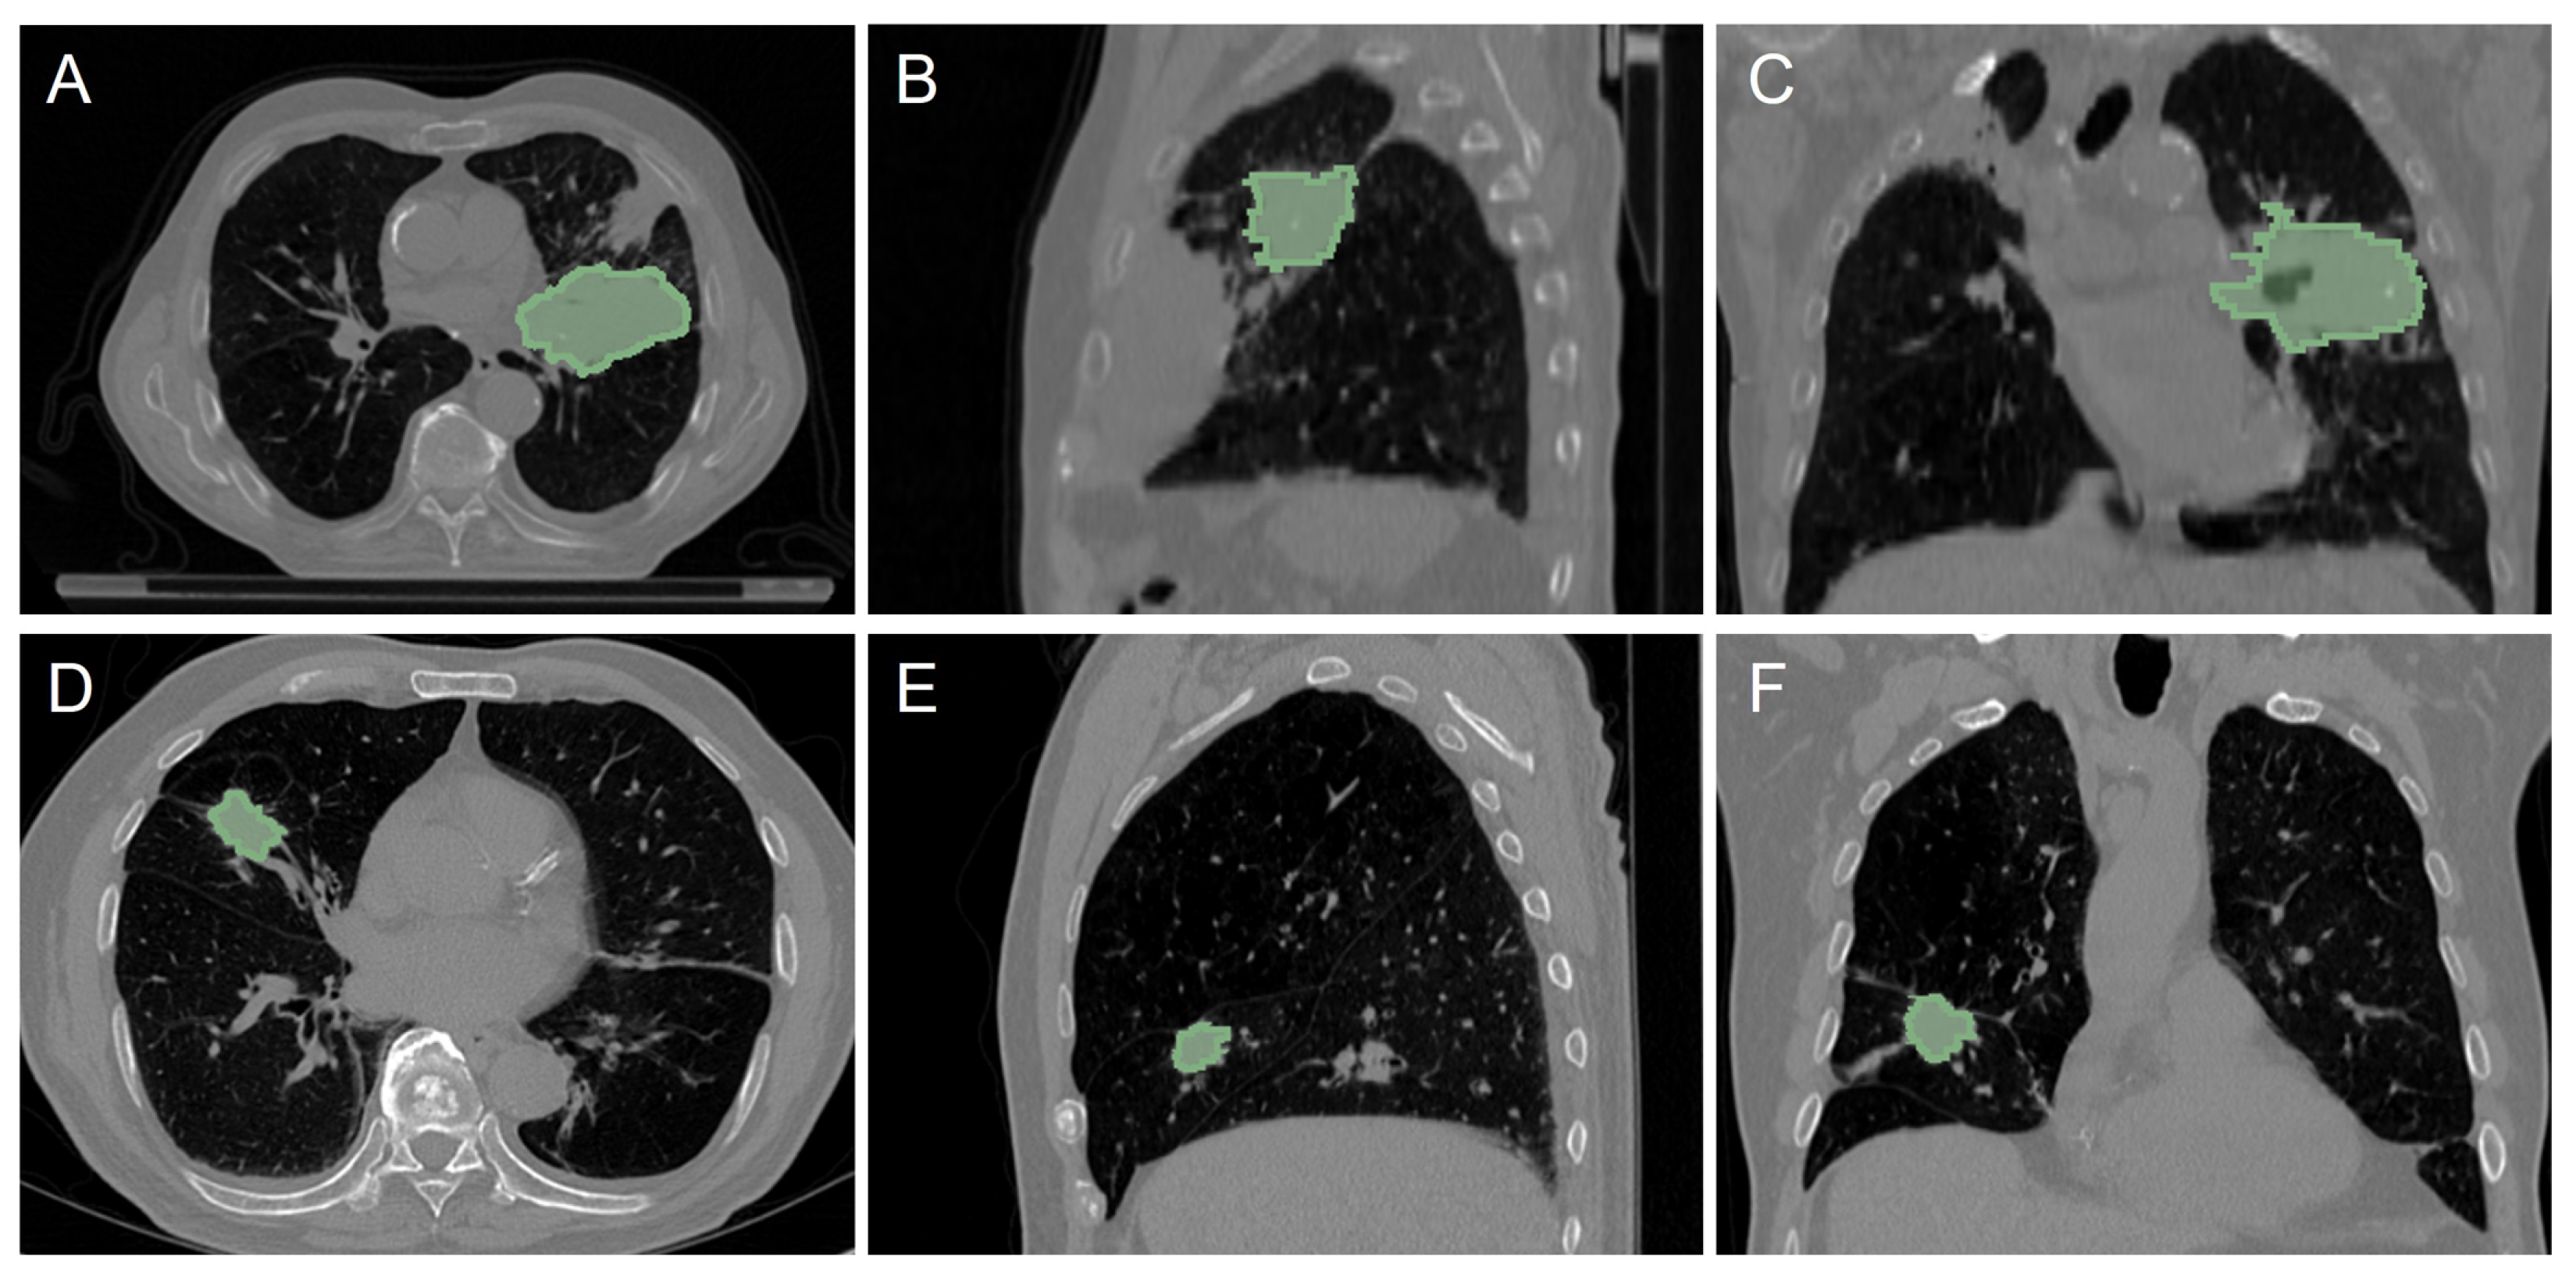

2.1. CT Dataset from NSCLC Patients